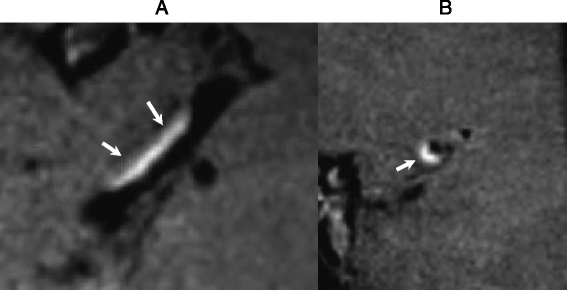

Utility of 3D BBMRI. Postcontrast 3D BBMRI images (acquired resolution, 0.52 mm isotropic) of the left middle cerebral artery (MCA) M1 segment in a 48 year old man with hypertension, diabetes, and coronary artery disease who presented with acute on subacute left MCA territory infarctions. Long axis (a) and short axis (b) reconstructions demonstrate eccentric thickening and intense enhancement of the M1 segment vessel wall (arrows)

Specific vessel wall characteristics that are sought on VWI include vessel wall thickening (smooth, irregular, circumferential, concentric, eccentric), signal, and enhancement [4]. A short axis view perpendicular to an intracranial vessel is best for evaluation of vessel wall thickening and pattern of enhancement (Fig. 1b). In this text we review the major current applications of BBMRI in the intracranial circulation.